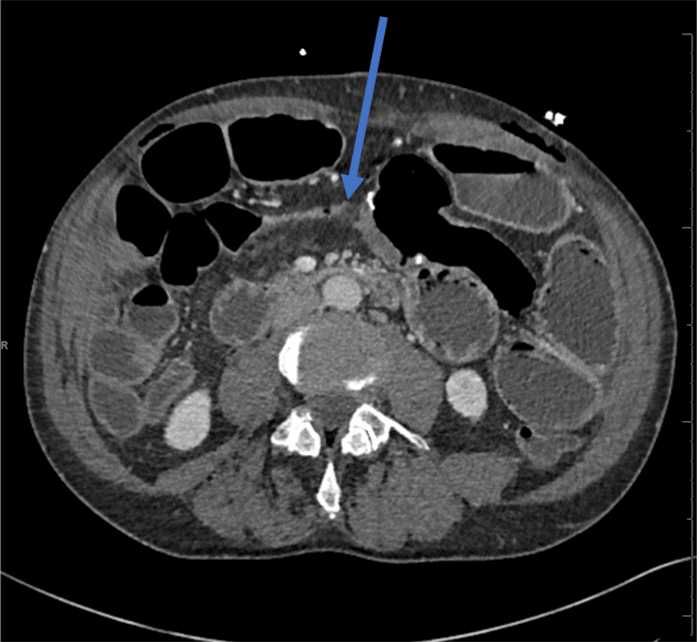

A CT scan demonstrated dilated small bowel loops with air-fluid levels, gastric distention, and a small segment of decompressed small bowel proximal to the patent anastomosis (Figure 3). A water-soluble upper GI study on POD 11 confirmed contrast passage into the colon. Persistent, copious watery diarrhea was noted, with negative C. difficile testing, ruling out a mechanical obstruction.

Figure 3. Abdominal and Pelvic CT Scan on POD 10. Published with Permission

Note dilated small bowel loops and a segment of decompressed small bowel proximal to the ileocolic anastomosis (blue arrow)